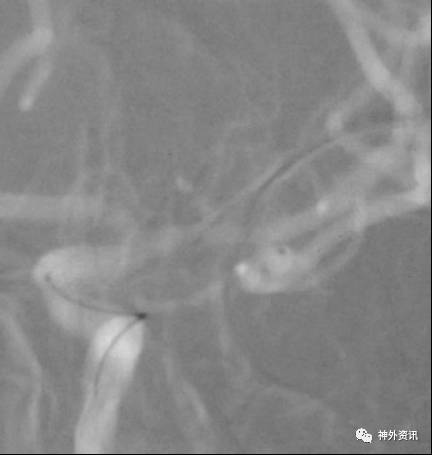

复合立体塑形

塑形考虑血管走行,但是血管内径过大(约>3mm,例如颈内动脉)的情况下,微导管在血管内是螺旋前进(2维是折线前进),即使顺行也需要考虑改变角度。

非同一平面内的弯曲:

(1)指向前方或后方的前交通动脉瘤

(2)指向前方或后方的大脑中动脉分叉部位动脉瘤

病例一

病例二

病例三